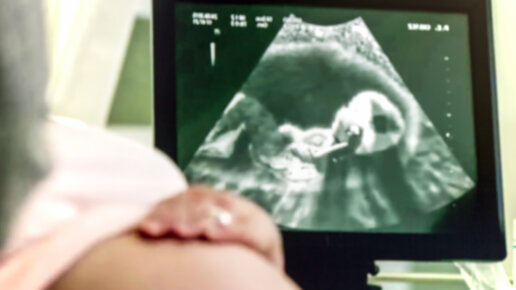

Что чувствует малыш в утробе?

Если вы думаете, что малыш в утробе только и делает что спит, вы ошибаетесь! Слушает музыку, смотрит на свет, наслаждается сладким, зевает и икает — каких только дел у него нет. Слух Биение материнского сердца, бурление кишечника, голос мамы, звонок телефона, голос из телевизора — все это дает нагрузку на уши плода в 60-70 децибел. Проведите эксперимент: наберите полную ванну воды, оставьте кран открытым на полную мощность и нырните с головой — примерно то же слышит ребенок в матке. При сильном...